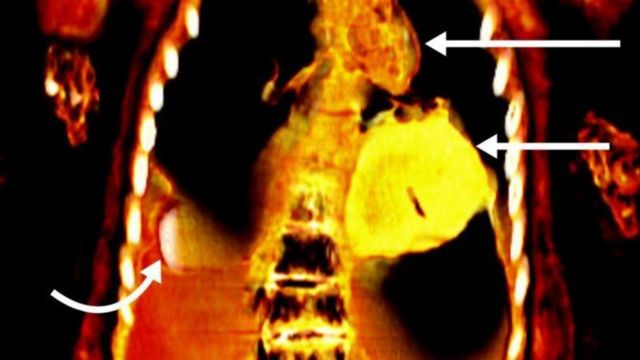

2,300 ஆண்டுகளுக்கு முன்பு பண்டைய எகிப்து நாகரிகத்தின் உயர் வகுப்பைச் சேர்ந்த பதின்ம வயது சிறுவன் ஒருவரின் உடல் தங்க இதயத்துடன் பதப்படுத்தப்பட்டிருப்பது ஆராய்ச்சியில் கண்டுபிடிக்கப்பட்டுள்ளது. 14 அல்லது 15 வயதில் இறந்ததாகக் கருதப்படும் இந்த சிறுவனின் உடல் 1916ஆம் ஆண்டு கண்டெடுக்கப்பட்டு, கெய்ரோவில் உள்ள எகிப்திய அருங்காட்சியகத்தில் டஜன் கணக்கான மம்மிகளுடன் வைக்கப்பட்டிருந்தது. ஒரு நூற்றாண்டுக்கும் மேலாக இந்த உடல் வல்லுநர்களால் முழுமையாக ஆய்வு செய்யப்படாமல் இருந்த நிலையில், கெய்ரோ பல்கலைக்கழகத்தைச் சேர்ந்த சஹர் சலீம் தலைமையிலான குழு சிடி ஸ்கேனரை பயன்படுத்தி மம்மியை ஆய்வு செய்தபோது இந்த உண்மை தெரியவந்துள்ளது. இந்த உடலில் 21 வகையான 49 தாயத்துகள் இருந்தது இந்தச் சோதனையில் தெரியவந்துள்ளது. அதில், பெரும்பாலானவை தங்கத்தால் ஆனவை. இதன் காரணமாகவே இந்த மம்மிக்கு `தங்க பையன்` என்று பெயரிட்டதாக ஃப்ரென்டியர்ஸ் இன் மெடிசின்(Frontiers in Medicine) என்ற சஞ்சிகையில் வெளியான கட்டுரையில் சலீம் கூறியுள்ளார்.

மேலும், உயர்தரம் வாய்ந்த பதப்படுத்தல் செயல்முறை மூலம் அவரது உடலின் எச்சங்கள் பதப்படுத்தப்பட்டுள்ளது. எனவே ஸ்கேன் முடிவுகள் இந்தச் சிறுவன் உயர்வகுப்பைச் சேர்ந்தவர் என்பதை உறுதிசெய்துள்ளது. அந்த இளைஞனின் உடலை மூடியிருந்த உறைக்குக் கீழே இரண்டு விரல்கள் அளவிற்கு நீளம் கொண்ட ஒரு பொருள் முன்தோல் நீக்கப்படாத ஆண்குறிக்கு அருகில் இருந்தது. மேலும், வாயில் ஒரு தங்க நாக்கு இருந்தது.

பட மூலாதாரம்,COURTESY SN SALEEM, SA SEDDIK, M. EL-HALWAGY

மம்மி

கடந்த காலங்களில், மம்மிகளில் இருந்து கவச உறைகள் அகற்றப்பட்டு, ஆராய்ச்சி மற்றும் பொழுதுபோக்கு நோக்கங்களுக்காக அவை சிதைக்கப்பட்டதாக சலீம் கூறுகிறார். ஆனால், தற்போதுள்ள கம்ப்யூட்டட் டோமோகிராஃபி (computed tomography) நுட்பம், மம்மிகளை சேதப்படுத்தாமல் ஆய்வு செய்ய ஒரு சிறந்த கருவியாக மாறும் என்றும், இது பண்டைய கால மனிதர்களின் ஆரோக்கியம், நம்பிக்கைகள் மற்றும் திறன்கள் குறித்து கூடுதலாக ஆராயவும் உதவும் என்கிறார் சலீம். "கம்ப்யூட்டட் டோமோகிராஃபி கதிரியக்க துறையில் ஏற்பட்ட குறிப்பிடத்தக்க முன்னேற்றத்தைக் காட்டுகிறது. ஒரு படத்தைப் பயன்படுத்துவதற்குப் பதிலாக, இதன் மூலம் உடலின் சிறு பகுதிகளின் நூற்றுக்கணக்கான கணிப்புகளை ஒன்றிணைத்து முழுமையான முப்பரிமாண மாதிரியை உருவாக்க முடியும்" என்றும் சலீம் கூறுகிறார்.